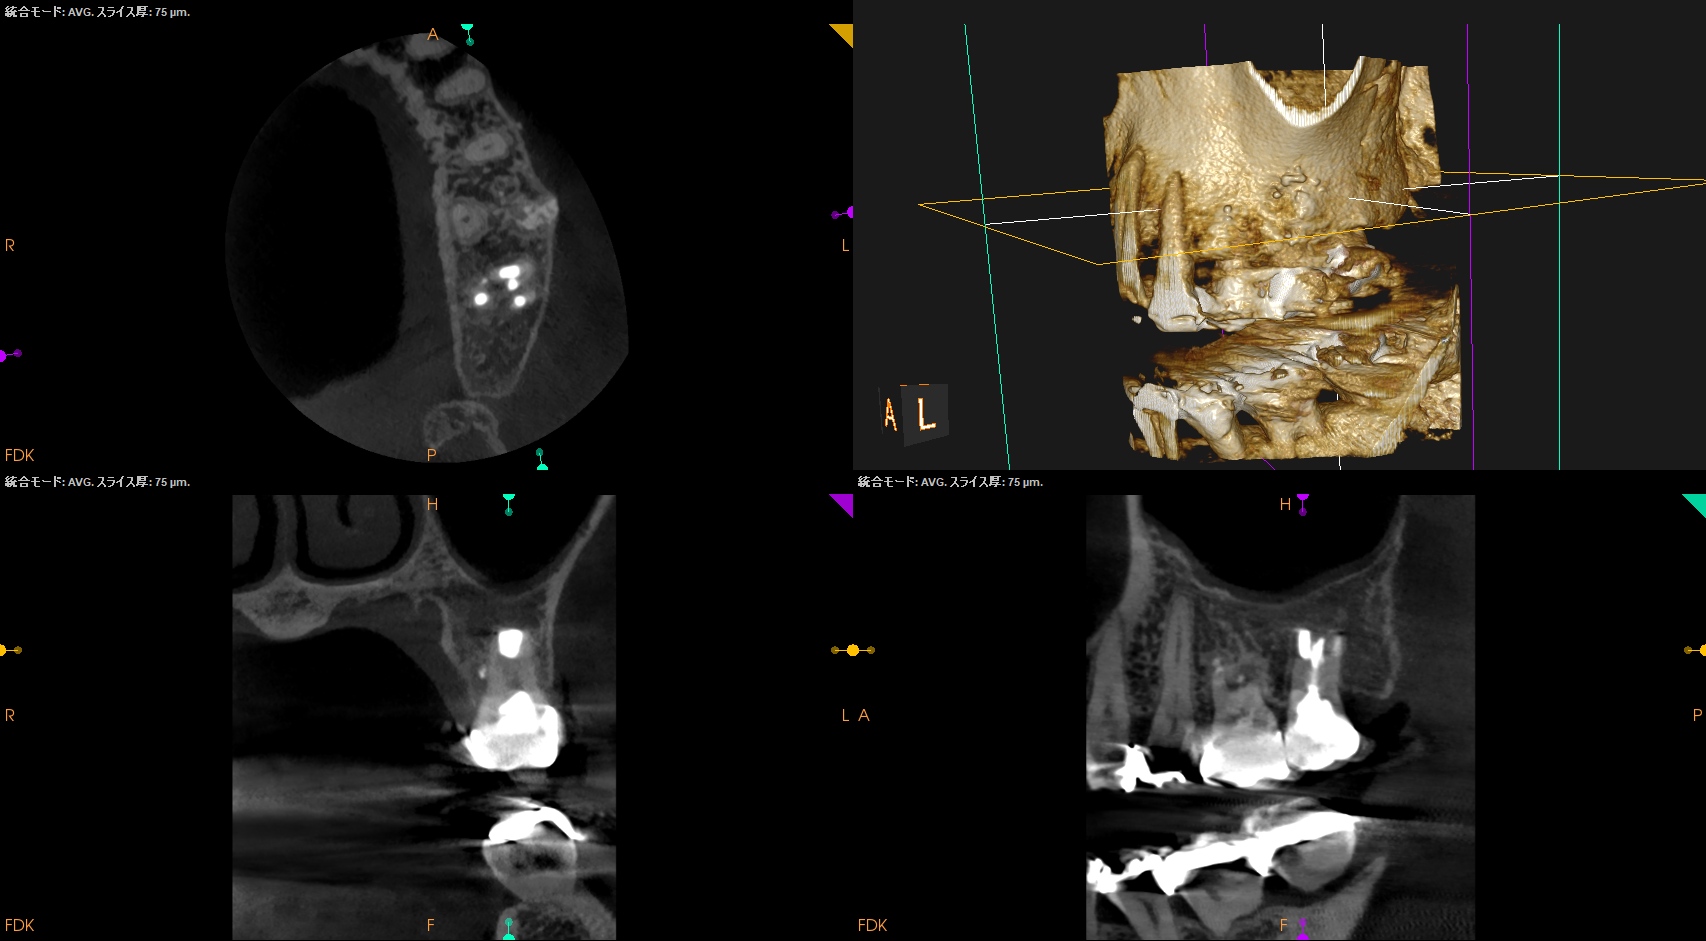

CBCT(2025.11.5)

MB

DB

P

Perforation site

治療前/直後と1年後を比較した。

完治だ。